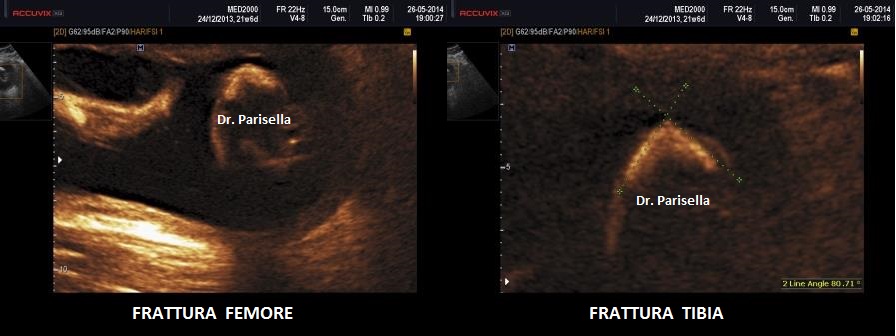

Quella che interessa dal punto di vista della diagnosi ecografica prenatale è l'Osteogenesi Imperfetta tipo II (OMIM 166210) caratterizzata da fragilità ossea con fratture multiple, micromelia severa dovuta alle fratture delle ossa lunghe, ipoplasia toracica severa a volte con fratture costali, ipomineralizzazione diffusa del cranio.  Ecograficamente si manifesta con ossa corte, ricurve e fratturate (le ossa fratturate si presentano angolate); ossa craniche scarsamente ossificate (tanto che la volta cranica può avere una ecogenicità simile a quella della linea mediana) con conseguente migliore evidenza e definizione delle strutture cerebrali e segno caratteristico la deformabilità della teca cranica.;  ipoplasia toracica con fratture costali; IUGR; movimenti fetali scarsi.